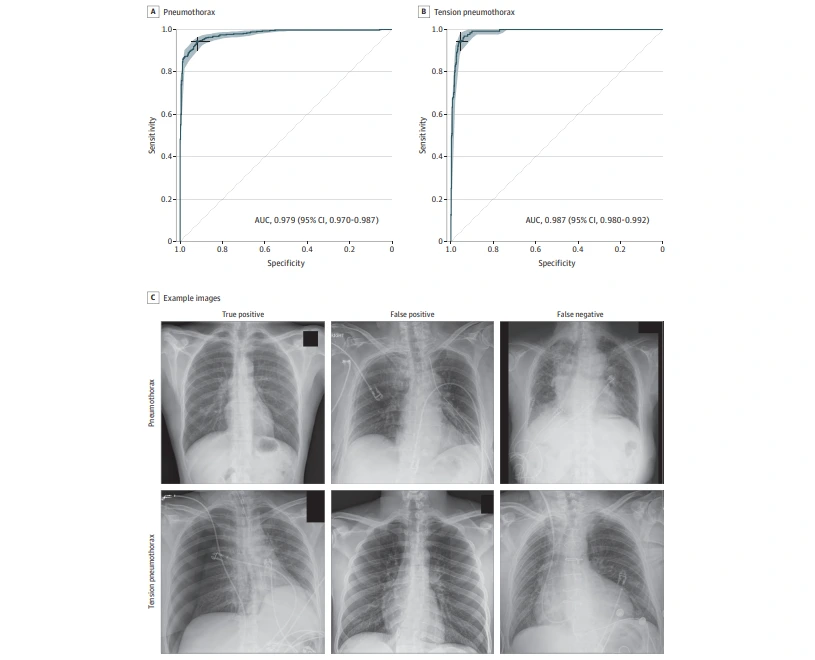

[참고 그림]

기흉 및 긴장성 기흉 검출을 위한 AUC 영역 및 예제 이미지

칼럼 이미지 캡처.PNG 논문 원문 자료 캡처

검증된 모델은 상용 버전으로 75만 건 이상의 흉부 영상으로 학습되었고 100가지 이상의 영상 소견을 찾을 수 있는 모델인데, 이 논문에서 이 모델은 기흉인지 아닌지, 혹은 긴장성 기흉인지 아닌지를 2진 분류법으로 구분하는 결과만 제공했다고 합니다. 테스트 데이터 985건에 대해서 기흉이 435건, 긴장성 기흉이 128건이었고, 11종의 X-ray 기계로 찍힌, 다양한 임상 소견으로 포함한 흉부 X-ray 영상에서 대략적으로 AUC 0.95, 민감도, 특이도는 80% 이상의 소견을 보여주고 있습니다. 자세히 살펴보면 X-ray 기종들 사이의 성능 편차가 좀 있긴 합니다(기종이 궁금하신 분은 논문을 직접 보시길). 긴장성 기흉은 AUC가 더 높은데, 기흉이 포함된 데이터셋에서 긴장성 기흉만 잘 골라냅니다. 흉부 수술 흔적, 배액관, 여러 라인들이 영상에 포함된 경우에도 AUC가 0.9 이상으로 대체적으로 높아 다양한 임상상황에서도 쓰일 수 있다는 것을 증명하였고 이에 기흉의 조기 발견 및 치료에 대한 기대감을 높였습니다.